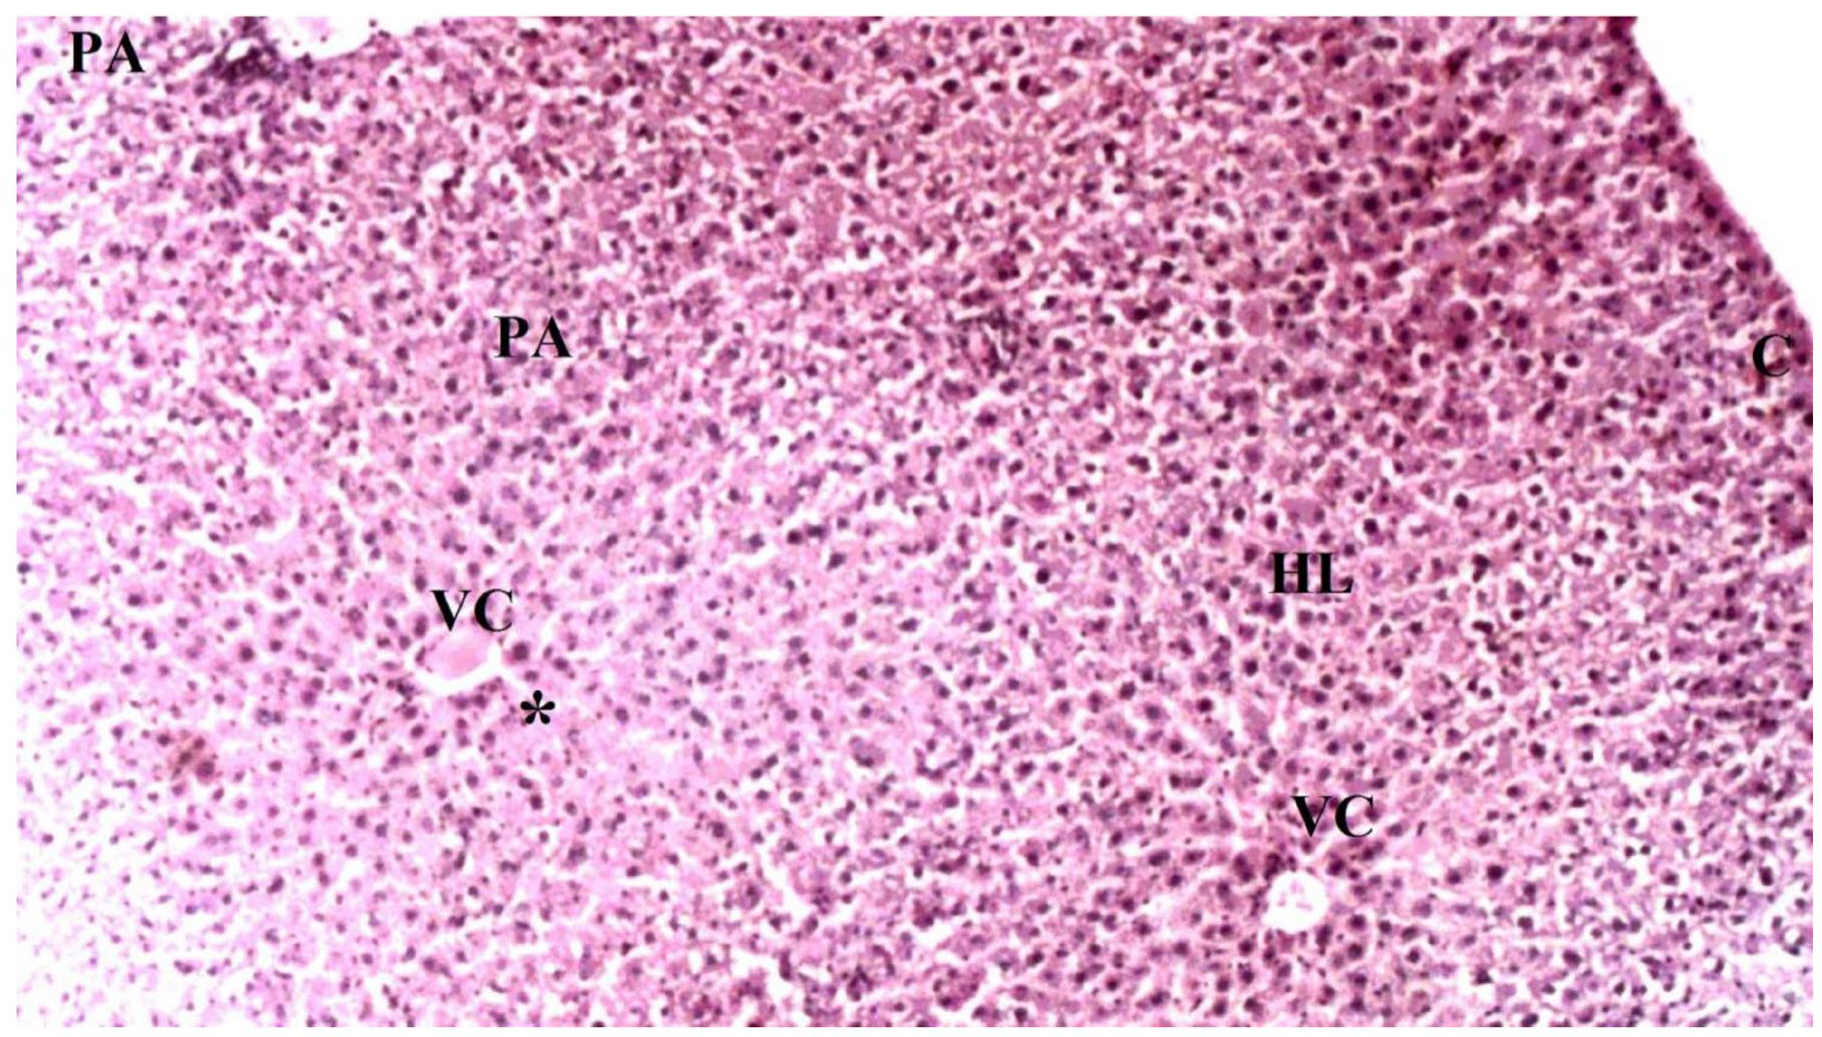

2.3. Liver